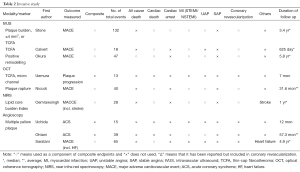

The common outcomes reported in the coronary atherosclerosis are summarized in Tables 1 and 2, which illustrate significant heterogeneity in the definition of outcomes, not only the variety in definitions of MACE but the inclusion or exclusion of all-cause mortality and unstable angina in various trials. There is also further fragmentation of definitions with some trials including only angina requiring hospitalization vs. requiring intervention vs. all angina. Clearly the presence of “stenosis >50%” on angiography does not carry the same weight as “cardiac death”. Given predictive value of a test is clearly influenced by the outcome measured it should serve as a caution pertaining to the subsequent discussion and indeed in any assessment of outcome measures.

The follow-up duration in a clinical study closely parallels the era when a modality becomes available for widespread-use. Table 1 clearly illustrates how CAC/CA score, CTCA, Plaque assessment and cMRA all have progressively lower/shorter durations of follow-up. As such any differences in event rates need to be interpreted in light of this follow-up period. From an invasive perspective, this difference is mirrored in the paucity of predictive supporting OCT compared to IVUS (Table 2).